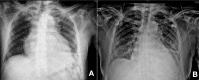

Pericardial effusion has a broad spectrum of clinical presentation, ranging from an incidental finding on imaging to a potentially fatal emergency such as pericardial tamponade, the most severe presentation. The authors present a case of a middle-aged male hospitalized due to shortness of breath. Initial work-up was positive for massive pericardial effusion with haemodynamic compromise. Additional study revealed panhypopituitarism. The acromegalic phenotype was suggestive of acromegaly secondary to pituitary adenoma, which had probably evolved to apoplexy. Hormone replacement was started with clinical improvement. At the 3-year follow-up, there was no evidence of recurrence of pericardial effusion. Panhypopituitarism is a relatively rare entity, but can lead to life-threatening complications such as adrenal crisis, coma and myxoedema-associated cardiac failure. Pericardial effusion is an extremely rare manifestation of secondary hypothyroidism.